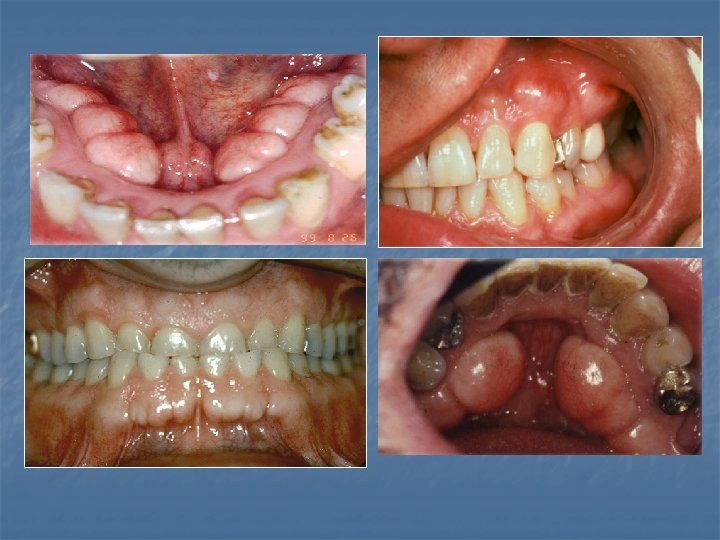

Exostoses n n n Localized boney protuberances that arise from the cortical plate. The best known are the torus palatinus and the torus mandibularis. Most often discovered in adults: Buccal exostoses: a bilateral row of boney hard nodules along the facial aspect of the max and mand alveolar ridge. Palatal exostoses (palatal tubercles) occur along the lingual aspect of max tuberosities. Solitary exostoses; may occur in response to local irritation. May develop beneath free gingival or skin grafts. May see Reactive Subpontine exostosis which may develop from alveolar crest bone

Torus Palatinus n n n A common exostosis that occurs in the palatal vault in the midline. Sometimes classified according to their morphology: Flat torus has a broad base and a smooth surface; Spindle torus has a midline ridge along the palatal raphe; Nodular torus has multiple protuberances that may coalesce forming grooves; Lobular torus has a lobular mass that may arise from a singular base. Most are small (less than 2 cm) but they can increase in size throughout life. They are usually asymptomatic however the overlying mucosa can become irritated secondary to trauma. Most studies show a prevalence of 20 -35% with a female: male ratio of 2: 1. the prevalence peaks during early adult life tapering off in later years showing these are dynamic lesions. Surgical removal is indicated if they become irritated and tramatized or fabrication of a denture base.

Torus Mandibularis n n n A common exostosis that develops along the lingual portion of the mandible. Above the mylohyoid in the premolar region, bilateral in 90% of cases. Can appear on periapical radiographs superimposed over the roots of the teeth. Prevalence 5 -40% depending on the study, more common in Asians and Inuit. Prevalence peaks in early adult life and tapers in later years. It also correlates with bruxism and remaining teeth which supports it’s response to functional stress. Surgery may be needed to accommodate a lower denture.